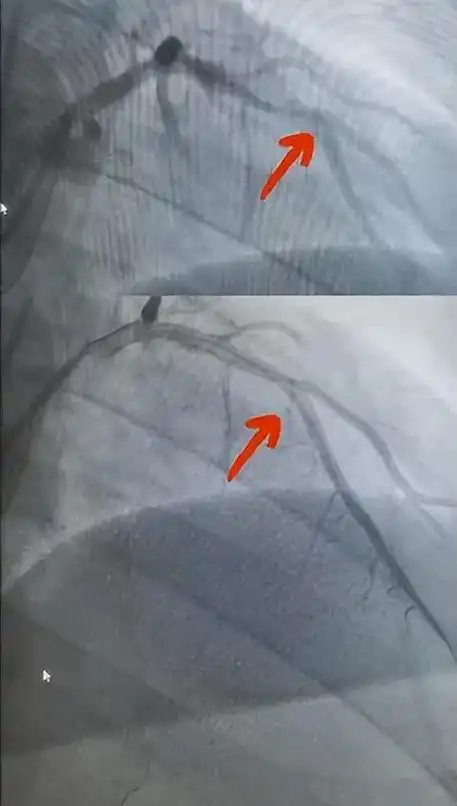

冠状动脉造影,左冠状动脉造影

冠脉造影提示:左冠状动脉的前降支也有重度狭窄

图2 急诊冠脉造影(右前斜 头位)